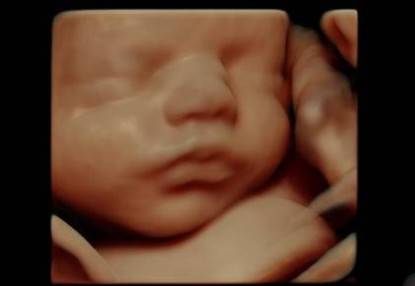

Presto le ecografie in 3D dei nostri piccoli ancora in grembo e di cui tanto siamo orgogliosi diventeranno obsolete perché anche in Italia sta per diffondersi l’ecografia 4D.

Fino a questo momento la scansione in 3D ci offriva un fermo immagine del feto in 3 dimensioni, ora con l’ecografia in 4D si potrà osservare il piccolo muoversi in tempo reale.

L’immagine diventerà poi più nitida e completa con l’aggiunta di una luce virtuale all’immagine grazie a un software HDLive che calcola la posizione delle ombre e la traslucenza della pelle del bambino.

A tutto ciò poi bisogna aggiungere l’assenza di rumori di fondo e il sapiente uso del colore e della luce per avere un’immagine più completa.